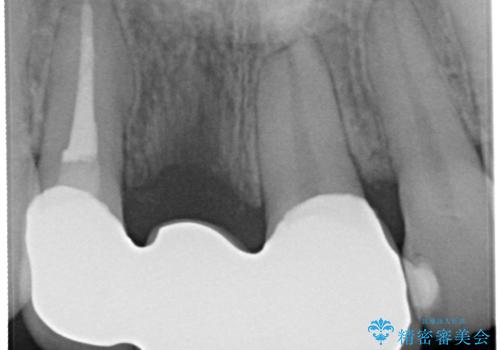

→根管治療のやり直しなどを経て、ブリッジを製作する。

古いかぶせ物は土台ごと歯から脱落してしまっており、歯の内面には複数の亀裂が入っている状態でした。残存歯質が非箔であることと、動揺の程度から、やむを得ず抜歯→ブリッジという方法を選択していただき、歯根挺出を用いることでなるべく前歯の骨の陥没を防ぎ、ブリッジを製作しました。

かぶせ物の種類:PFZ standard